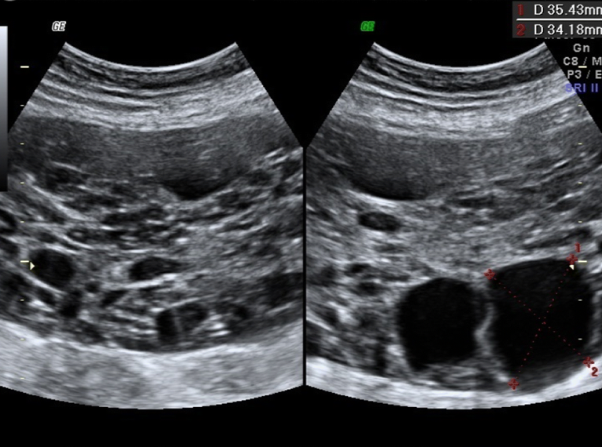

Maternal virilization during pregnancy is a rare phenomenon. Polycystic ovary syndrome (PCOS), luteoma and luteinic cysts are the most frequent and benign etiologies. This article presents two cases of recurrent maternal virilization during pregnancy.